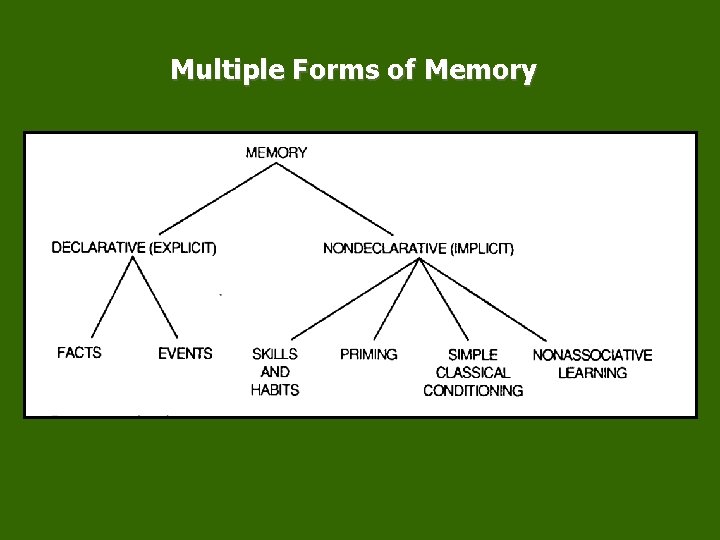

Multiple Forms of Memory